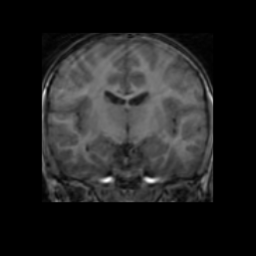

Accuracy is reported as Dice overlaps between a tool's segmentation and the Internet Brain Segmentation Repository (IBSR) manual segmentation for each of the 18 IBSR subjects. The inter-tool comparison (on the left below) shows the median Dice coefficient for each tissue class. The overlaps for FSL (from which the median values are drawn) are shown in the plot on the right.

Overlap coefficients for each tissue class are shown here for each IBSR subject. Select a subject below to see the FSL results compared to other tools.